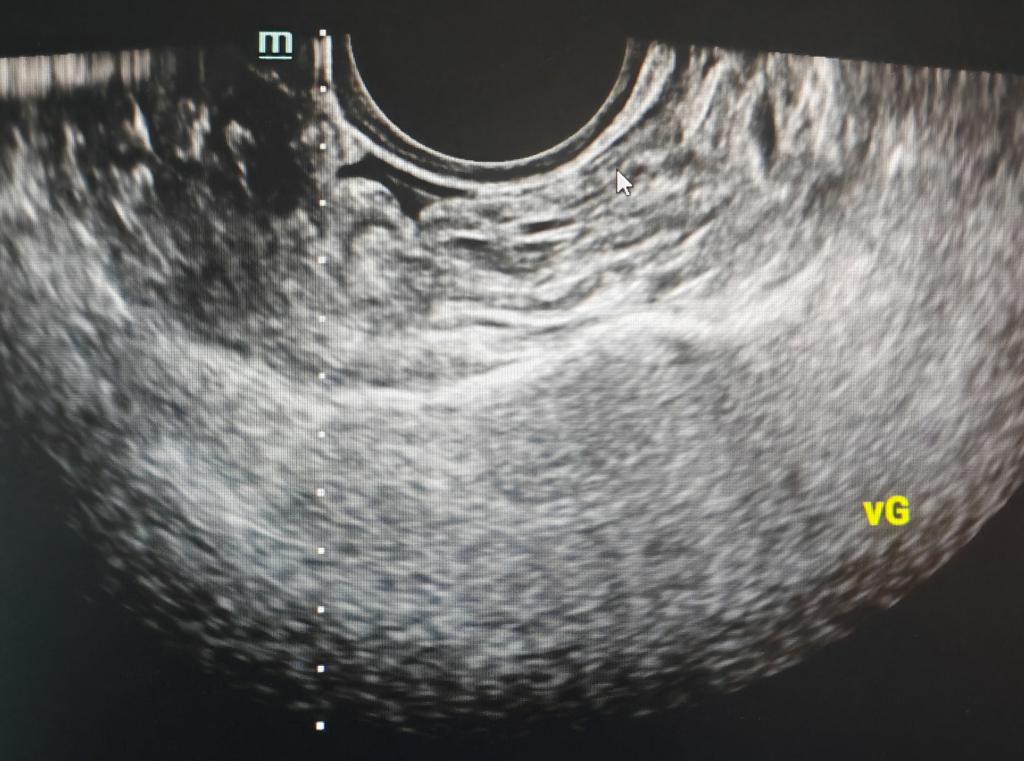

▲术中实时引导,针尖位于囊肿中

44岁女性,发现右侧附件囊肿数月,近期出现右脚麻木,既往有附件囊肿腹腔镜手术史,现复发不愿再次手术,于是到我科行穿刺硬化治疗。术前彩超、磁共振检查了解囊肿大小(68.5*43.5mm)、形态及位置毗邻,确定穿刺所需体位以及进针方向、深度,局部消毒后,在超声实时引导下,沿穿刺线精准刺入囊腔,用注射器共抽出90ml液体,蛋白定性试验阳性,冲洗干净后注入硬化剂,超声显示囊腔基本消失,术后盆腔无出血,双脚麻木立刻消失,体表无瘢痕,仅见一针眼。